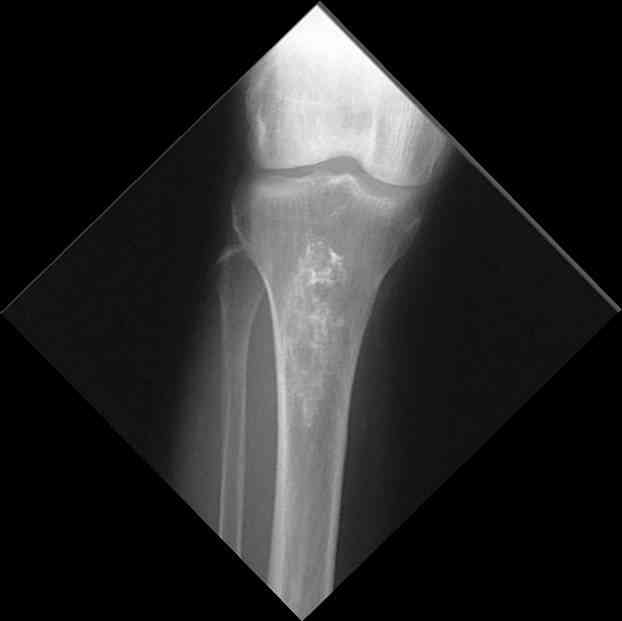

Для примера привожу случай из архива американской ассоциации рентгенологов (ACR) - развитие злокачественной фиброзной гистиоцитомы на левой б.берцовой кости у пациента с множественными инфарктами костного мозга (рис 4,5 - левая, рис 6 - правая)